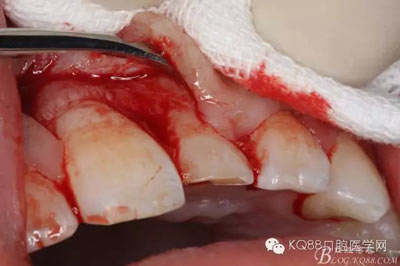

圖5.局部無(wú)痛麻醉下。行唇側(cè)齦溝內(nèi)切口

圖6.雙側(cè)垂直附加切口,形成梯形瓣

圖7.翻瓣、注意是全厚瓣。

圖8.翻開(kāi)牙齦粘膜瓣,可見(jiàn)左乳Ⅰ根方骨面隆起